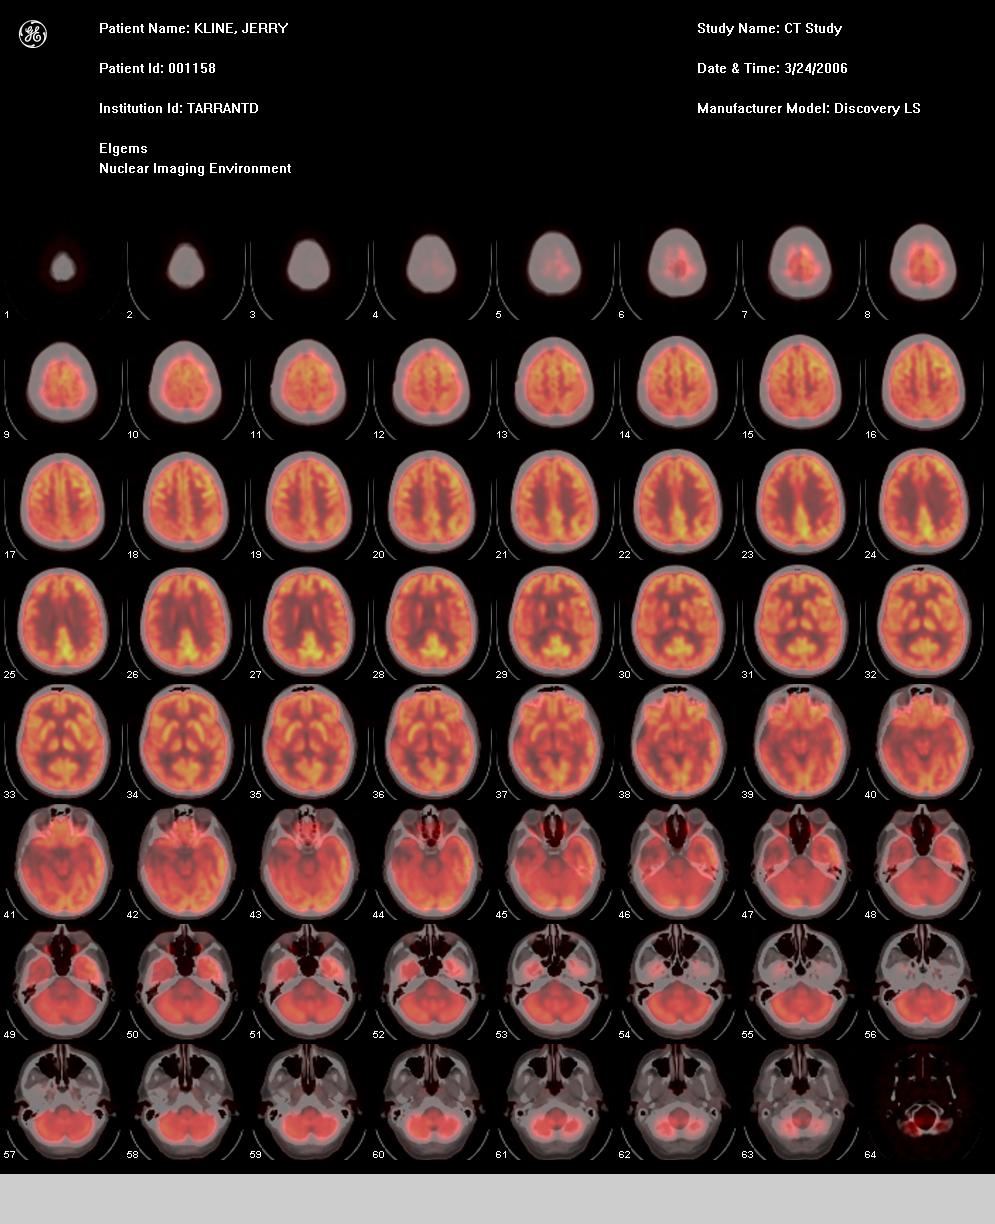

Transaxial Fused Images

Transaxial (top view) Fused images. Key elements to look for are color symmetry. Notice the dark areas representing my eyes.

I had my eyes closed, so minimal glucose consumption was occurring.

Transaxial PET Images

Transaxial PET images. I now have proof that there is indeed something (good) in my head, contrary to popular belief!